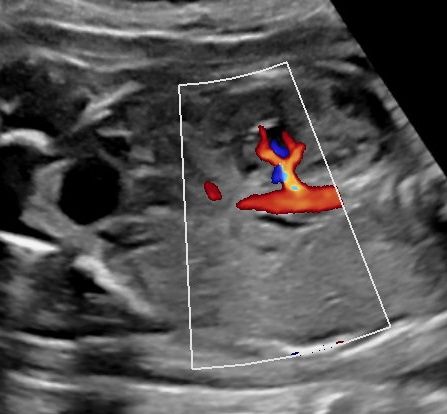

Sonoanatomie, Biometrie, Hinweiszeichen & Diagnose von Entwicklungsstörungen, Kasuistiken, ausreichend Zeit für Diskussionen, Fallbeispiele aus der Praxis (Quiz)